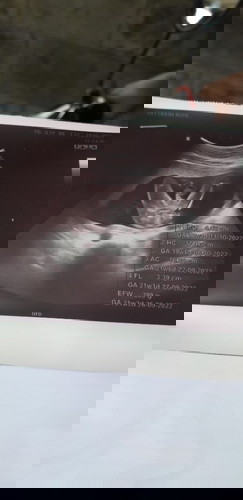

ท้องแรก....ได้ลูกชายเลยจ้า5555👶💖👪 โชว์จู๋เลยหรอลูก5555🤦♀️🤗

เห็นเพศน้องชัดเจน ไม่ต้องลุ้นเลยค่ะ